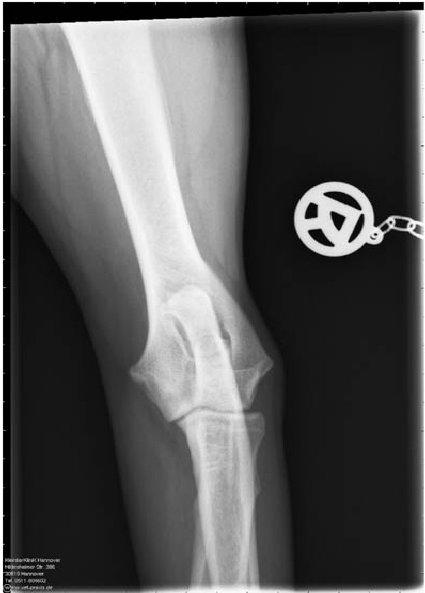

ED - OCD - Röntgenaufnahme